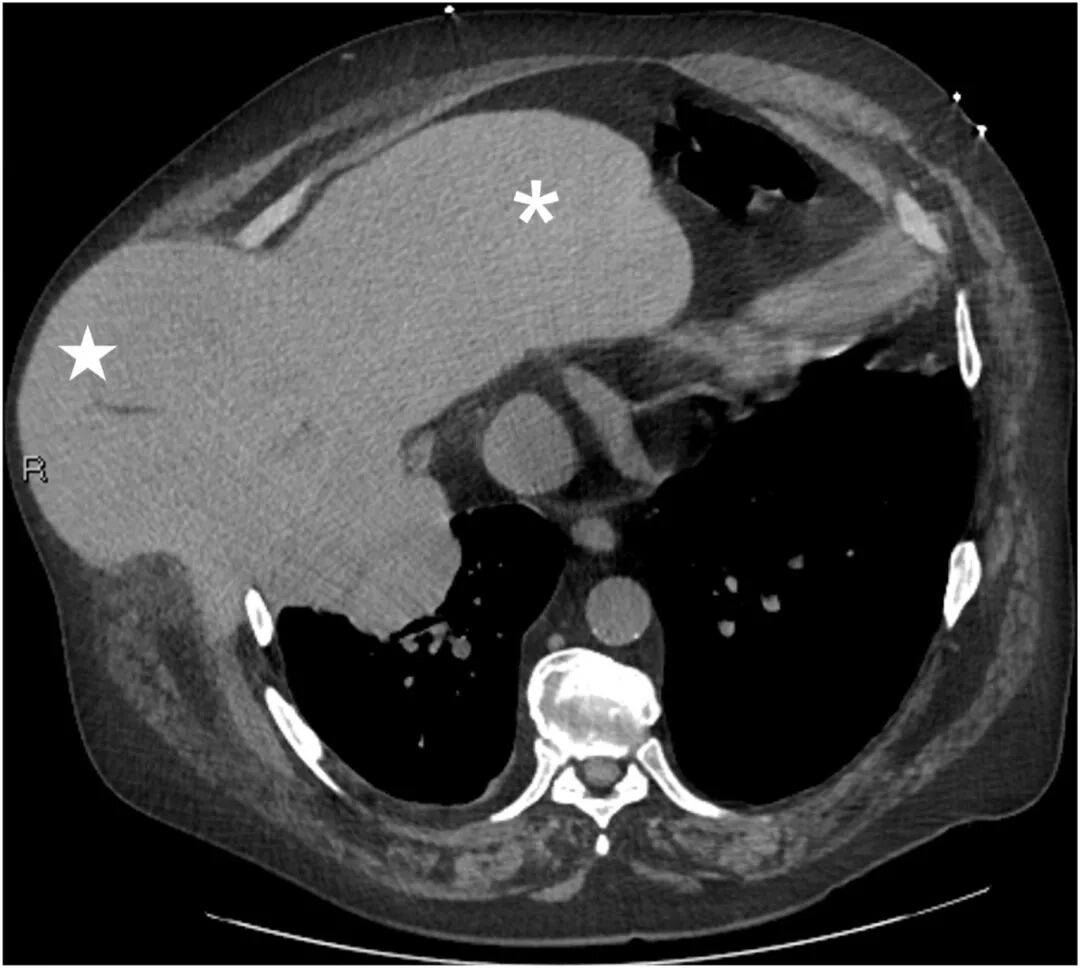

生命体征:血压126/91 mmHg,心率104次/分钟,未吸氧状态下血氧饱和度为 98%。体格检查发现,右上腹有一处无压痛、不可复位且可触及的隆起。行计算机断层扫描,如图1和图2所示。

图2:胸部对比增强计算机断层扫描(轴位)显示肝脏(星号标示)经胸壁和膈肌疝入胸膜腔(*号标示)。

诊断:腹壁肝疝。